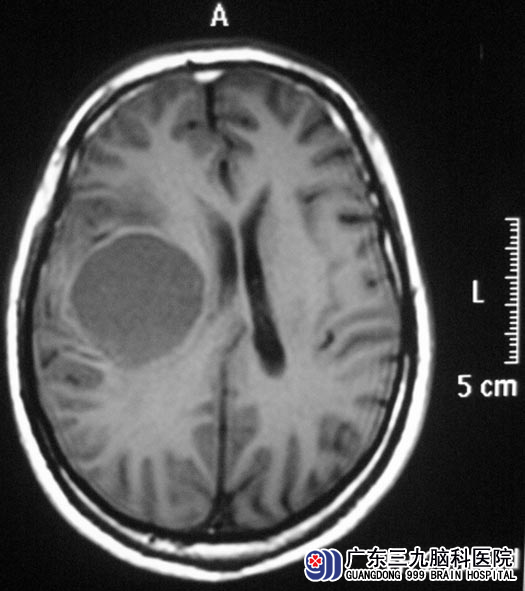

今年年后,李先生开始出现左侧肢体乏力,左手持物不能,言语欠清晰。这下李先生不敢再大意。广东三九脑科医院头颅MR结果提示:右侧额顶叶病变,直径约5cm,考虑胶质瘤复发可能。http://www.999brain.com/

▲手术前